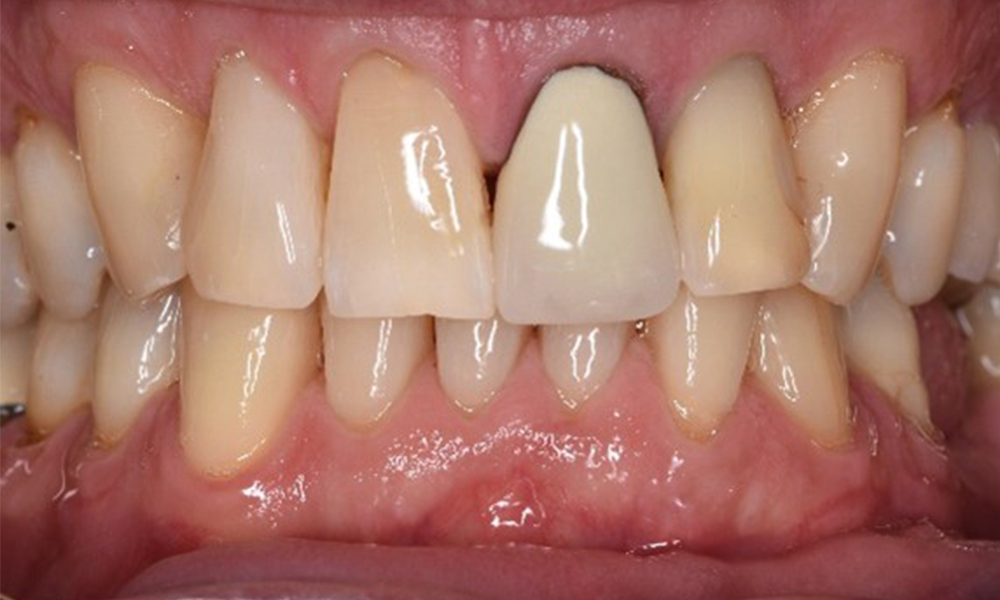

Der gesunde Patient mit parodontaler Vorerkrankung & Periimplantitis